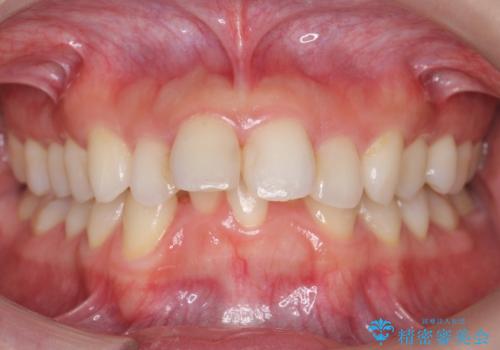

就職前にきれいな歯並びにしたい 大学生のインビザライン矯正

担当医 藤巻太一朗